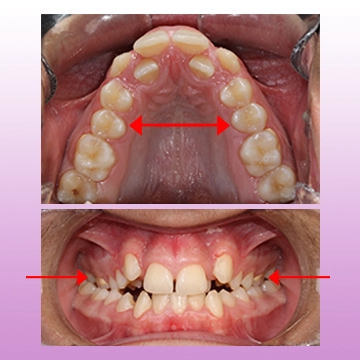

پیچ بازکننده فک بالا (RPE یا هایرکس)

در بسیاری از کودکان، فک بالای باریک یا تنگ دیده میشه که میتونه باعث شلوغی دندونها و حتی مشکلات تنفسی بشه.

پیچ بازکننده فک بالا یا هایرکس یک دستگاه ثابته که روی دندونهای بالا نصب میشه و به تدریج عرض فک بالا را افزایش میده.

مزایای هایرکس:

- ایجاد فضای کافی برای رویش دندونها

- بهبود تنفس

- کاهش احتمال کشیدن دندون

- اصلاح مشکلات جویدن